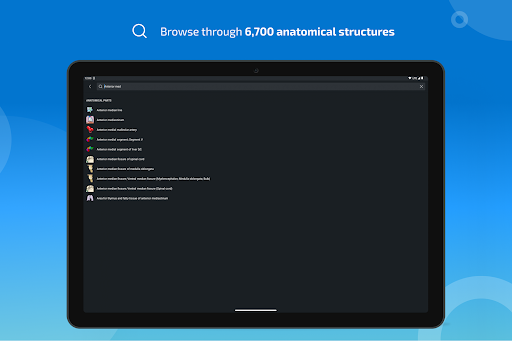

- Mudah menemukan struktur anatomi berkat pencarian indeks

*Temukan bagian anatomi Anda dengan lebih mudah berkat fitur pencarian baru yang lebih intuitif dan canggih